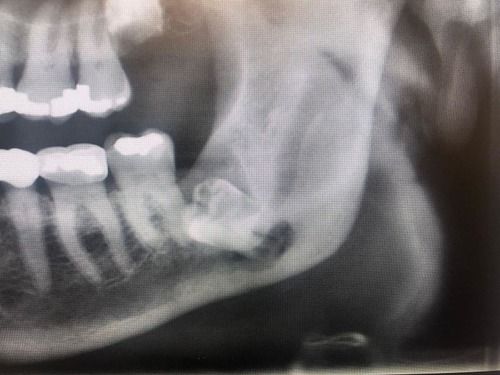

Impacted teeth can be associated with cysts and tumors, but the most common problem is infection. Less frequently, associated cysts can become infected or grow large enough to weaken the lower jaw. A weakened jaw can fracture with minimal trauma.

The removal of some deeply impacted teeth can decrease the integrity of the mandible, putting it at risk for fracture. (Image courtesy Nicolas S. Veaco, D.D.S., M.D., M.S.)

- Jaw softness: This is much less common. Impacted teeth can be associated with large cysts or chronic infection, which can weaken the lower jaw or interfere with standard drainage of the maxillary sinuses. When this happens, the end of the jaw remains more fragile while healing. Such an issue would appear during a routine examination with appropriate imaging. Returning to dive too early could increase the risk of fracture.